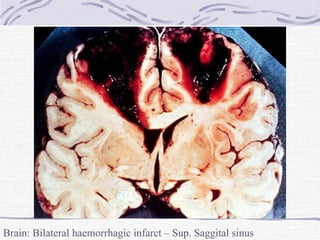

CNS Infarction Venous thrombosis Primary – non-infectious Pregnancy, puerperium and oral contraceptives Haematological disorders Extreme dehydration Haemorrhagic infarction Secondary – pyogenic infections Infections from sinuses, middle ear Compound fracture Septic infarction

Brain: Bilateral haemorrhagic infarct – Sup. Saggital sinus thrombosis